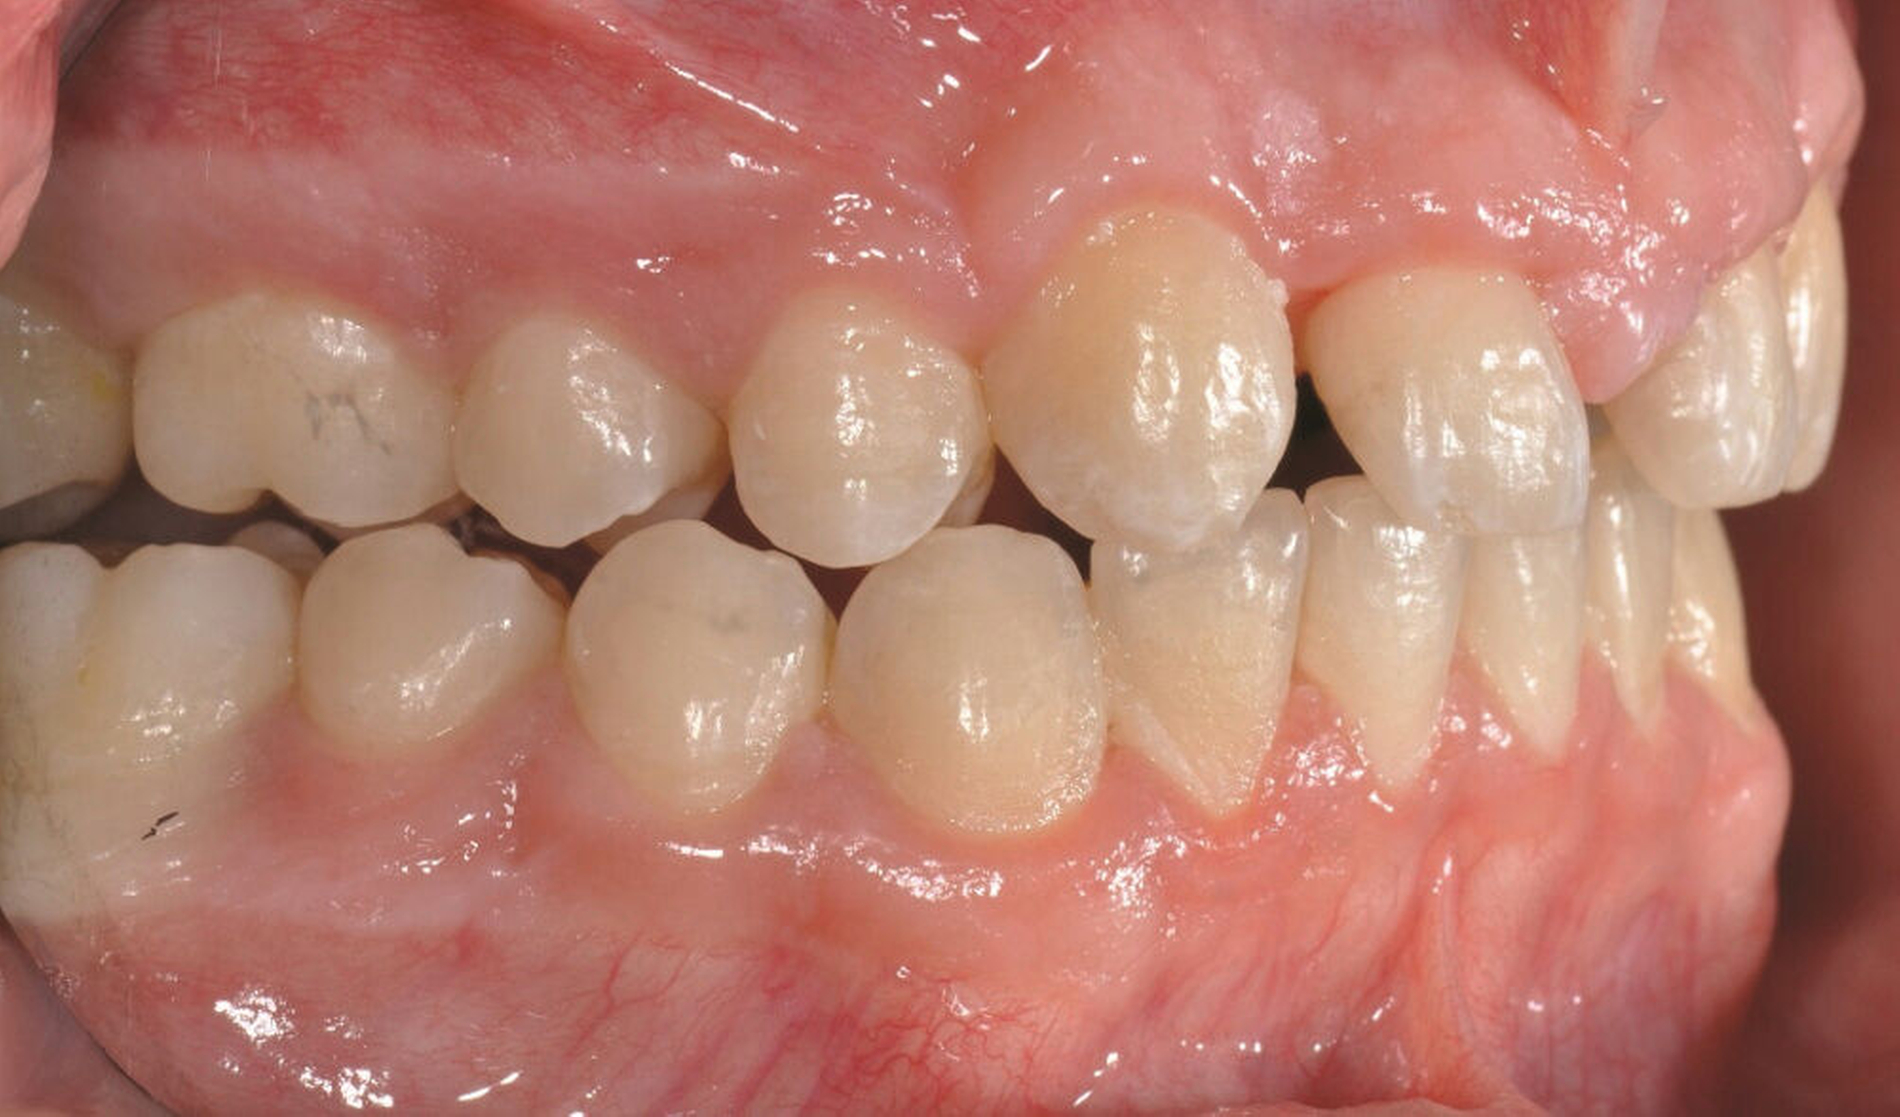

Bei der Erstvorstellung zeigt der Patient ein ausgeprägtes Diastema mediale sowie Restlücken und Asymmetrien im Oberkieferfrontzahnbereich nach kieferorthopädischer Therapie alio loco (Abbildung 1). Aufgrund mangelnder Adhärenz konnten nicht alle kieferorthopädischen Behandlungsziele erreicht werden, was insbesondere aus ästhetischer Sicht Herausforderungen für den restaurativen Lückenschluss mit sich bringt. Erschwerende Faktoren sind die Verschiebung der Mittellinie, die Achsenneigung der Zähne 13, 12, 22 und 23 sowie die inhomogene Lückenverteilung mit ungleich verteilten Lückengrößen (Abbildung 2). Eine erneute kieferorthopädische Korrektur lehnt der Patient allerdings ab. Subjektiv empfindet er insbesondere das kindliche Erscheinungsbild der lückig stehenden, kurz und klein wirkenden seitlichen Schneidezähne als störend. Ziele der Behandlung sind eine präventionsorientierte, ästhetisch-funktionale Rehabilitation des Oberkieferfrontzahnbereichs und eine Harmonisierung des dentofazialen Erscheinungsbildes.